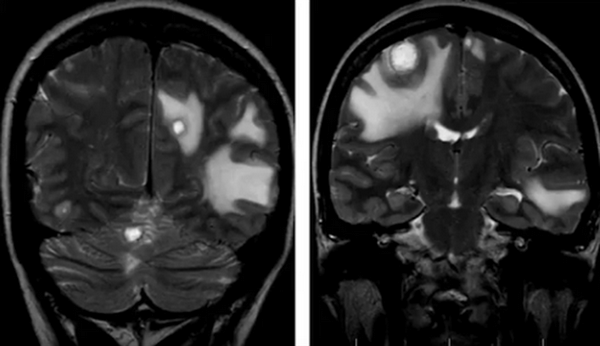

Метастазы в головном мозге на постконтрастном изображении (указаны стрелками)

Множественные метастазы в вещество головного мозга на МРТ без контраста

- метастазы. Выглядят, как множественные образования в тканях головного мозга различных размеров, неправильной формы, с неровными контурами, накапливающие контраст, с различной интенсивностью отека вокруг;